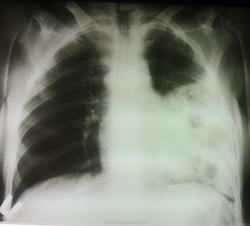

Больная доставлена СМП, флюроархива нет, больная асоциального вида, 1977 г.р. со слов больной болеет около месяца. температура 37.5 Интересует ваше мнение, коллеги...

Однородная инфильтрация, множественные полости распада.. Пневмония наверное с присоединением какой-нибудь небанальной флоры

Возможно, формируется абсцесс.

необычная форма затемнения. Напоминает петли кишечника.

Мне тоже показалась кишка

Сперва подумал о грыже с "начинкой из кишки". Пневмония тоже может быть.

А почему возникли мысли о "кишке"? Понимаю, что речь идет и крупных диафрагмальных грыжах, но куда деть четкий контур диафрагмы? Просветления на фоне инфильтрации очень напоминают полости распада при абсцедирующей верхнедолевой (язычковой) пневмонии, тем более что обзор брюшной полости не назначали, а значит и признаков патологии брюшной полости у пациентки нет? Не надо особо обольщаться асоциальностью, в наше время это не имеет уж такого большого значения!

Затемнение "вне анатомических границ". Покрутил бы за экраном, вывел бы на "контур", возможно получил бы осумкованный, или пневмоплеврит, возможно, с массивным обызвествлением костальной плевры.

тоже бросилось в глаза, что затемнение вне анатомических границ, за экраном покрутить не удалось, больная была "лежачая", очень истощенная.

Нашёл "трубу", связывающую этот клубок с брюшной полостью

Настоящая "труба".